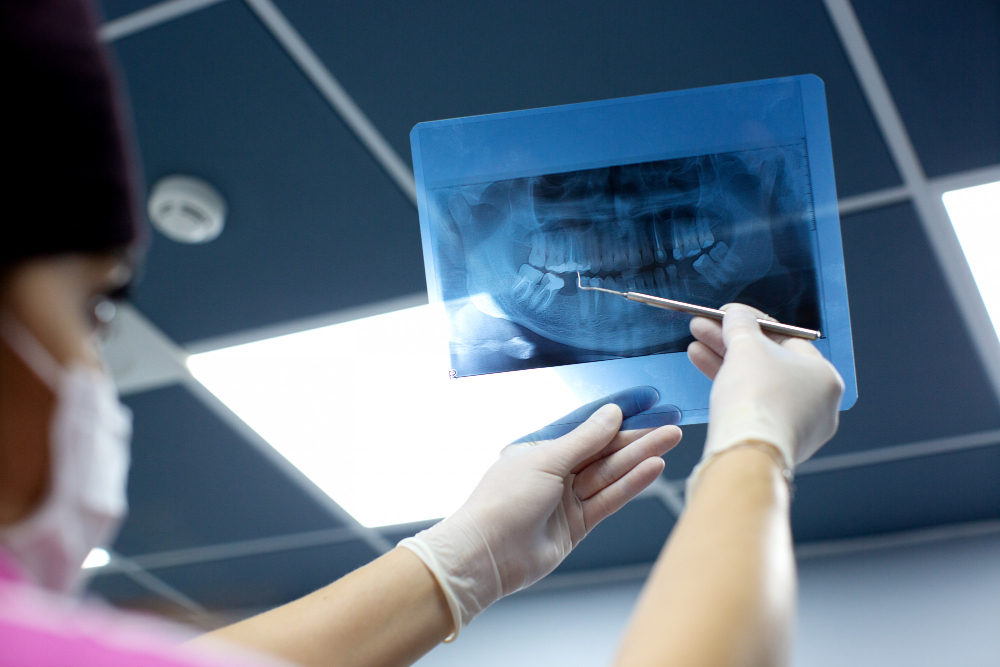

Dentists use several methods to find cracked teeth. First, they ask about your symptoms and examine your mouth. Next, they may use a bright light or magnifying glass to look for cracks. Sometimes, they use dental dye to highlight cracks. X-rays can help, but small cracks may not show up. In some cases, dentists use special tools to test how your tooth responds to pressure. Early diagnosis is important for the best dental crack treatment.